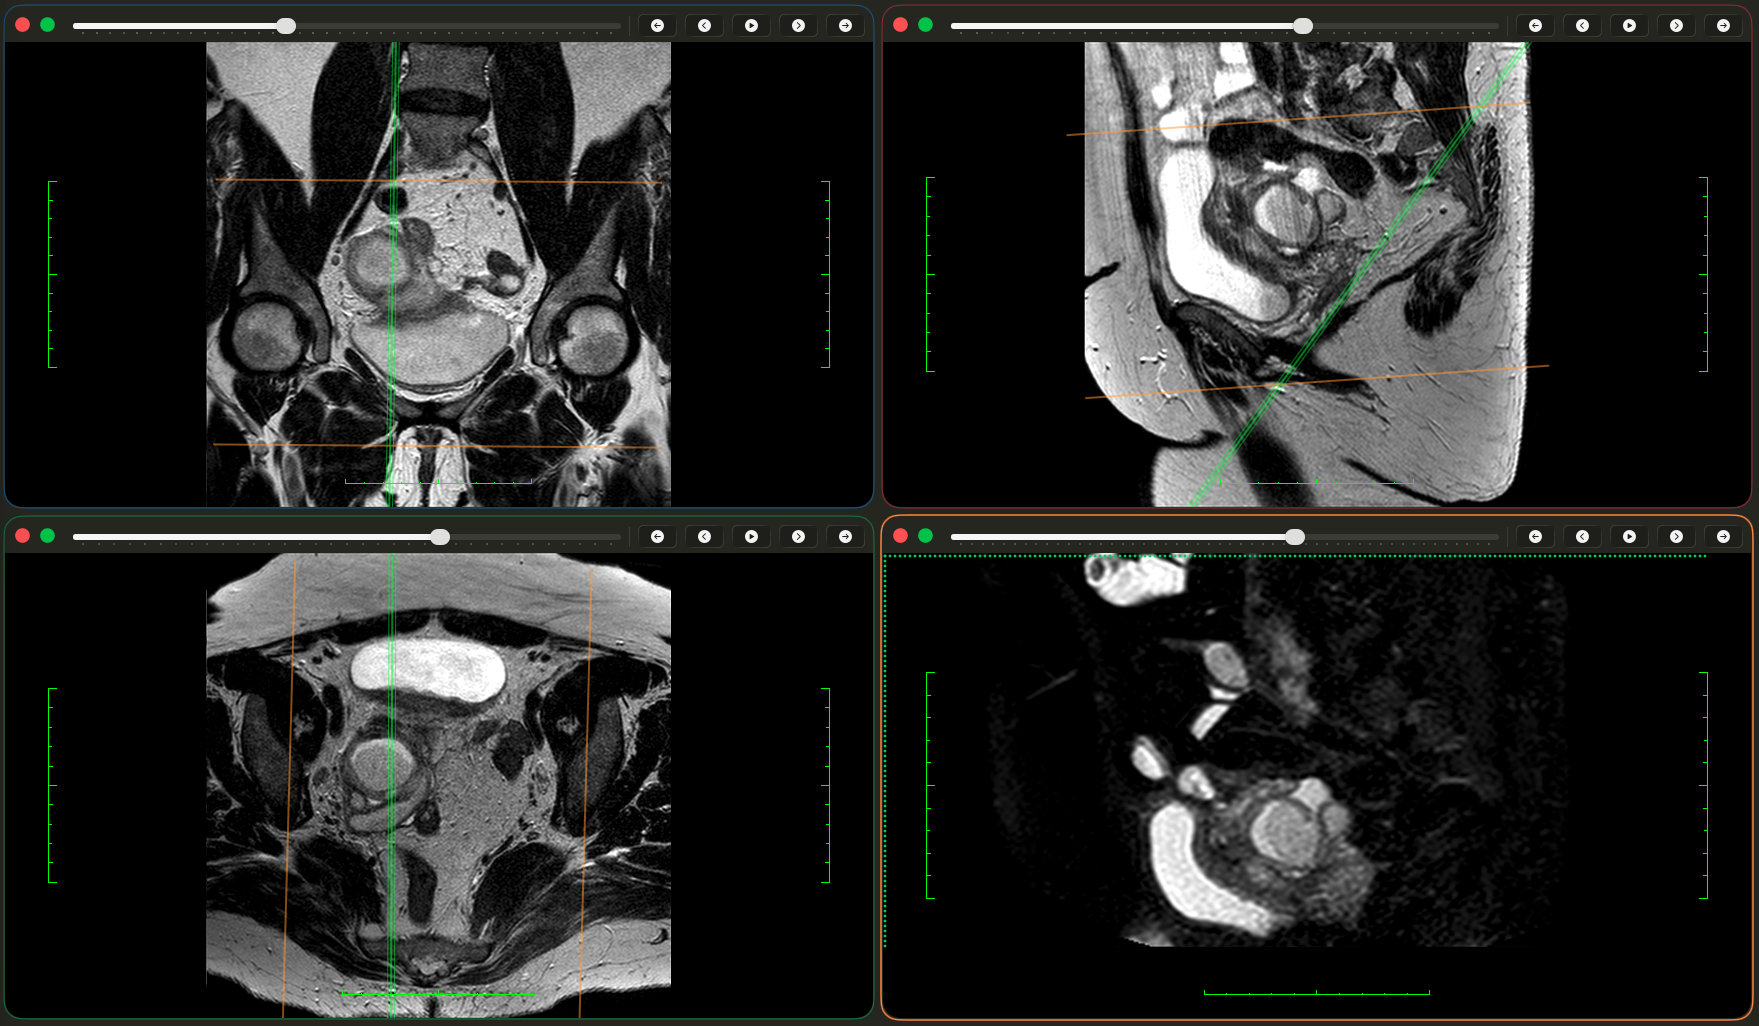

Пацієнтка 53 роки.

В анамнезі — екстирпація матки (12.2024) з приводу міоми.

Протягом року — ознаки хронічного запального процесу кукси піхви, виділення післяопераційних лігатур, проведення протизапальної терапії.

• за результатами дообстеження — утворення запального характеру в порожнині таза із залученням додатків

📌 Діагноз:

Тубооваріальне утворення додатків матки.

Відмежований хронічний тазовий перитоніт.

Лапароскопія. Видалення запального тубооваріального утворення додатків матки в умовах відмежованого хронічного тазового перитоніту. Санація черевної порожнини.

✔ розбір МРТ та клінічного висновку (зображення будуть доступні на сайті)